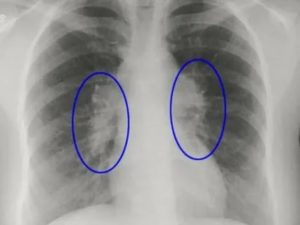

Увеличение лимфоузлов средостения на рентгенограмме выглядит как «патологическая тень», с помощью обследования доктор может сделать заключение о размещении очага воспаления или новообразования, его форме, подвижности. Также рентген помогает определить, оказывает ли заболевание негативное воздействие на внутренние органы, расположенные рядом.

Увеличение лимфоузлов средостения

Увеличенные лимфоузлы на рентгене часто изображены в форме уплотнений, часто патология сопровождается увеличением корней легких.

Процесс, воздействующий на лимфоузлы в легких, действует также на лимфатические узлы, расположенные рядом с бронхами и трахеей. Сложность их установления позволяет увидеть увеличение только путем рентгенологического исследования.

Но даже при этом не всегда удается полностью рассмотреть состояние узлов из-за ветвей легочных артерий или вследствие тени от сердца. Поэтому такое обследование проводят также в боковой проекции.